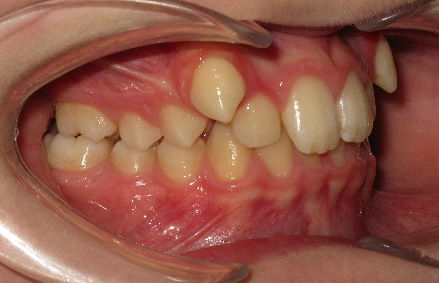

В полости рта: смыкание первых моляров по дистальному типу. Сужение зубных рядов в боковых отделах. 13 и 23 - вестибулярное и супраположение с дефицитом места в зубном ряду на величину ширины коронки клыка. Глубокая резцовая окклюзия.(рис.2.)

Рис.2.Смыкание зубных рядов пациента А. до лечения и окклюзионный вид.

После дистализации боковых сегментов на верхней челюсти и правильной постановки клыков в зубной ряд проведена фиксация аппарата на нижний зубной ряд и дальнейшая коррекция окклюзии проводится по стандартному протоколу, т.е. нормализация формы зубных рядов на верхней и нижней челюсти с правильной постановкой зубов по торку в боковых и во фронтальном отделах, что дает реализация программы, заложенная в пассивной самолигирующей брекет- системе NexStep Pro 0.22. (рис.8)